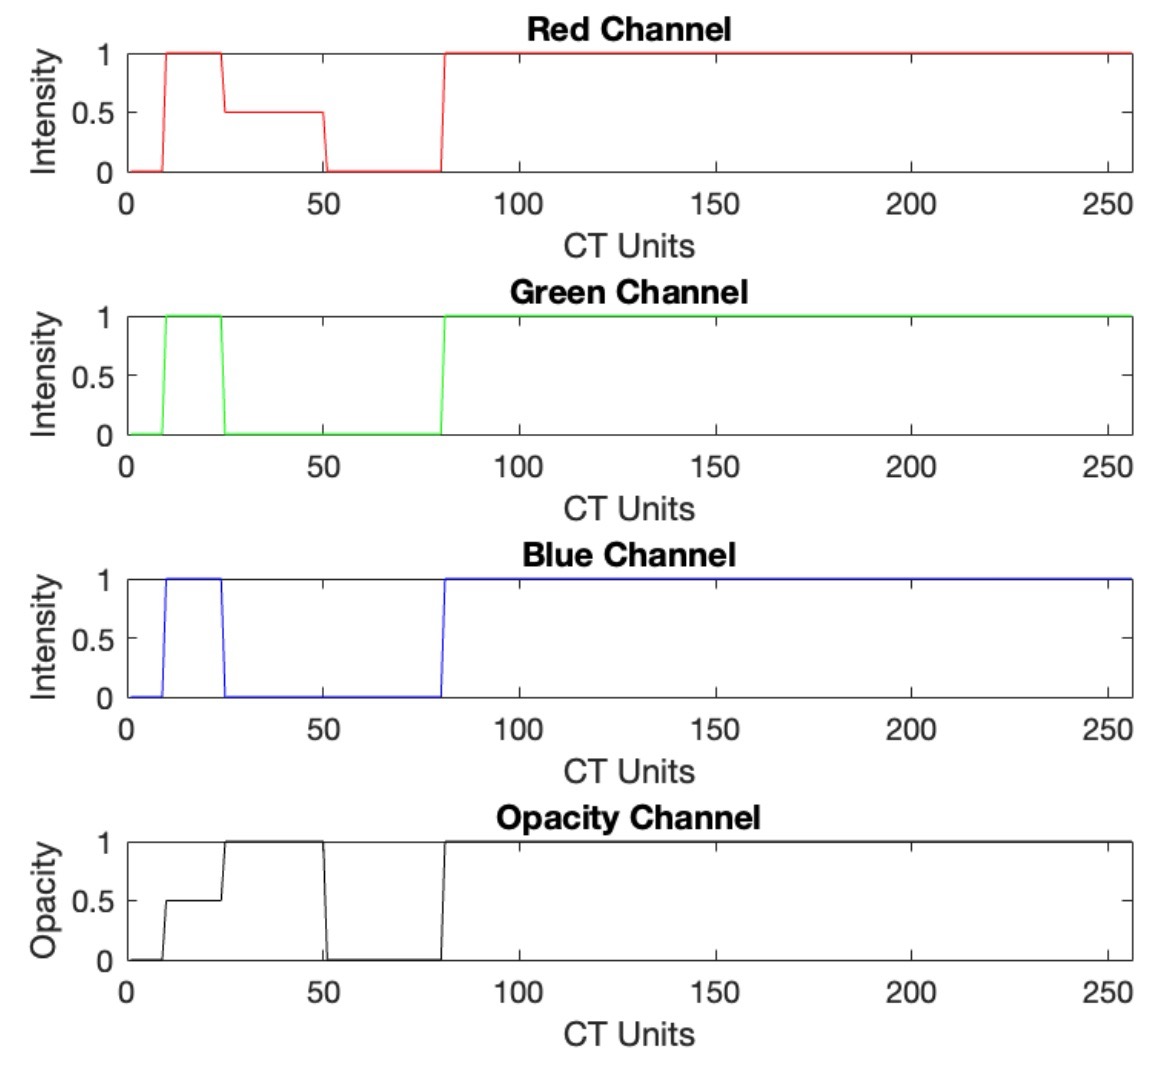

- Transfer Function Design: Created mappings from voxel intensity to RGBA values, enabling anatomical realism in CT renderings (bone, liver, fat).